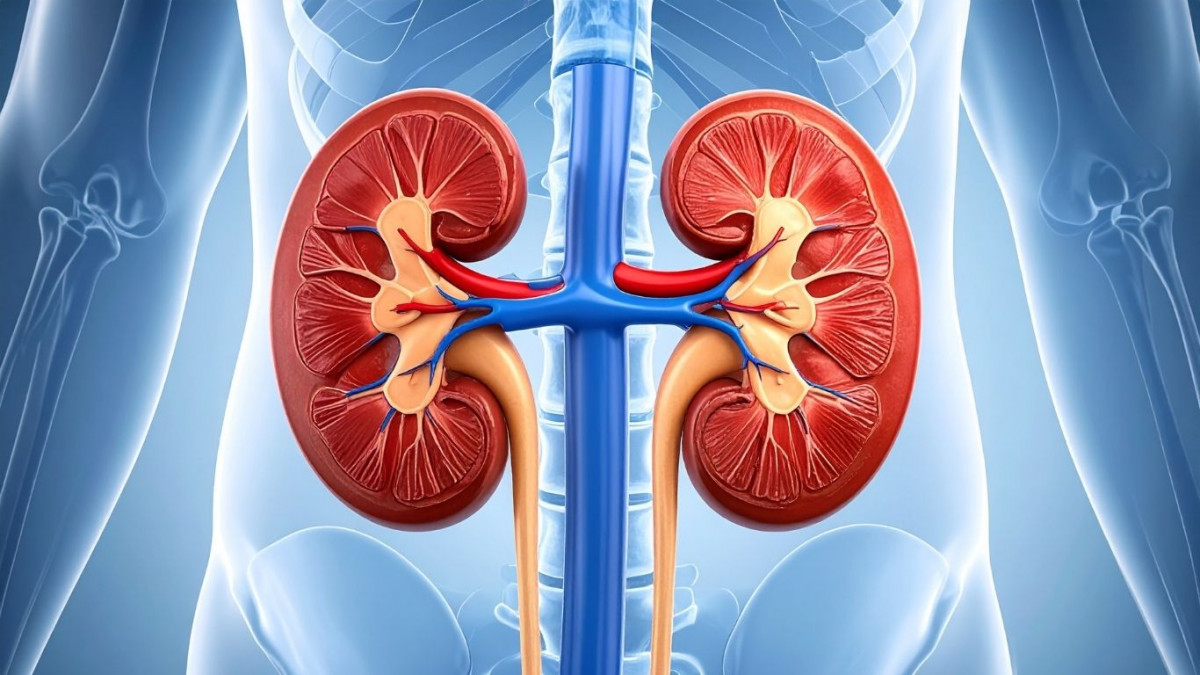

Kidney failure occurs when the kidneys can no longer perform their functions effectively, such as filtering metabolic waste, maintaining fluid balance, and regulating electrolytes in the body.

The kidneys play an important role in maintaining overall body balance by:

- Filtering metabolic waste from the blood

- Regulating fluid and electrolyte balance

- Controlling blood pressure

- Producing erythropoietin hormone to support red blood cell production [2.1]